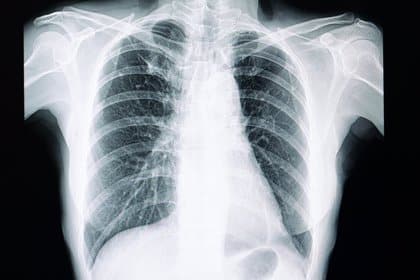

Efectos del ejercicio en pacientes con fibrosis pulmonar

La fibrosis pulmonar (FP) es causada por una variedad de factores, manifestándose con disnea, cansancio e intolerancia al ejercicio. Recientemente […]